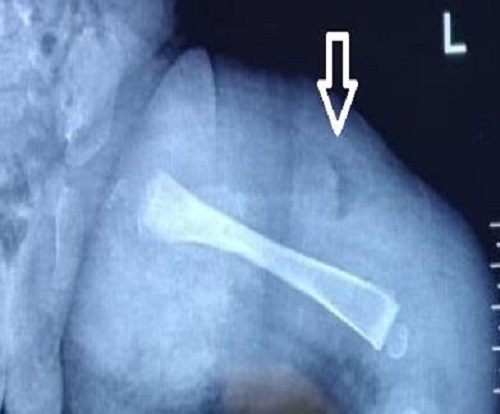

A month-old male baby presented with a complaint of left thigh swelling for 5 days and fever for 2 days. The baby had leukocytosis (TLC = 19200/uL) and a raised CRP (230 mg/L). X-ray Left thigh was within normal limits with only soft tissue changes (Fig. 2). There was a history of a local tap by a local practitioner, which was dry (as per records). Left thigh swelling gradually increased and the baby did not respond to first-line antibiotics for 4 days. Magnetic resonance imaging was planned in view of the suspicion of osteomyelitis and revealed bone marrow edema with osteopenia. There was diffuse edema of left thigh soft tissue with loss of fat planes and thickening suggestive of cellulitis changes. The baby underwent surgical drainage of the pus and received 2 weeks of antibiotics (i.v. and oral) in the postoperative period followed by oral antibiotics for 4 weeks. Pus culture had no growth. Baby is fine at a follow-up period of 2 years.

Figure 2

Early X-ray showing normal bone anatomy and soft tissue hypertrophy.